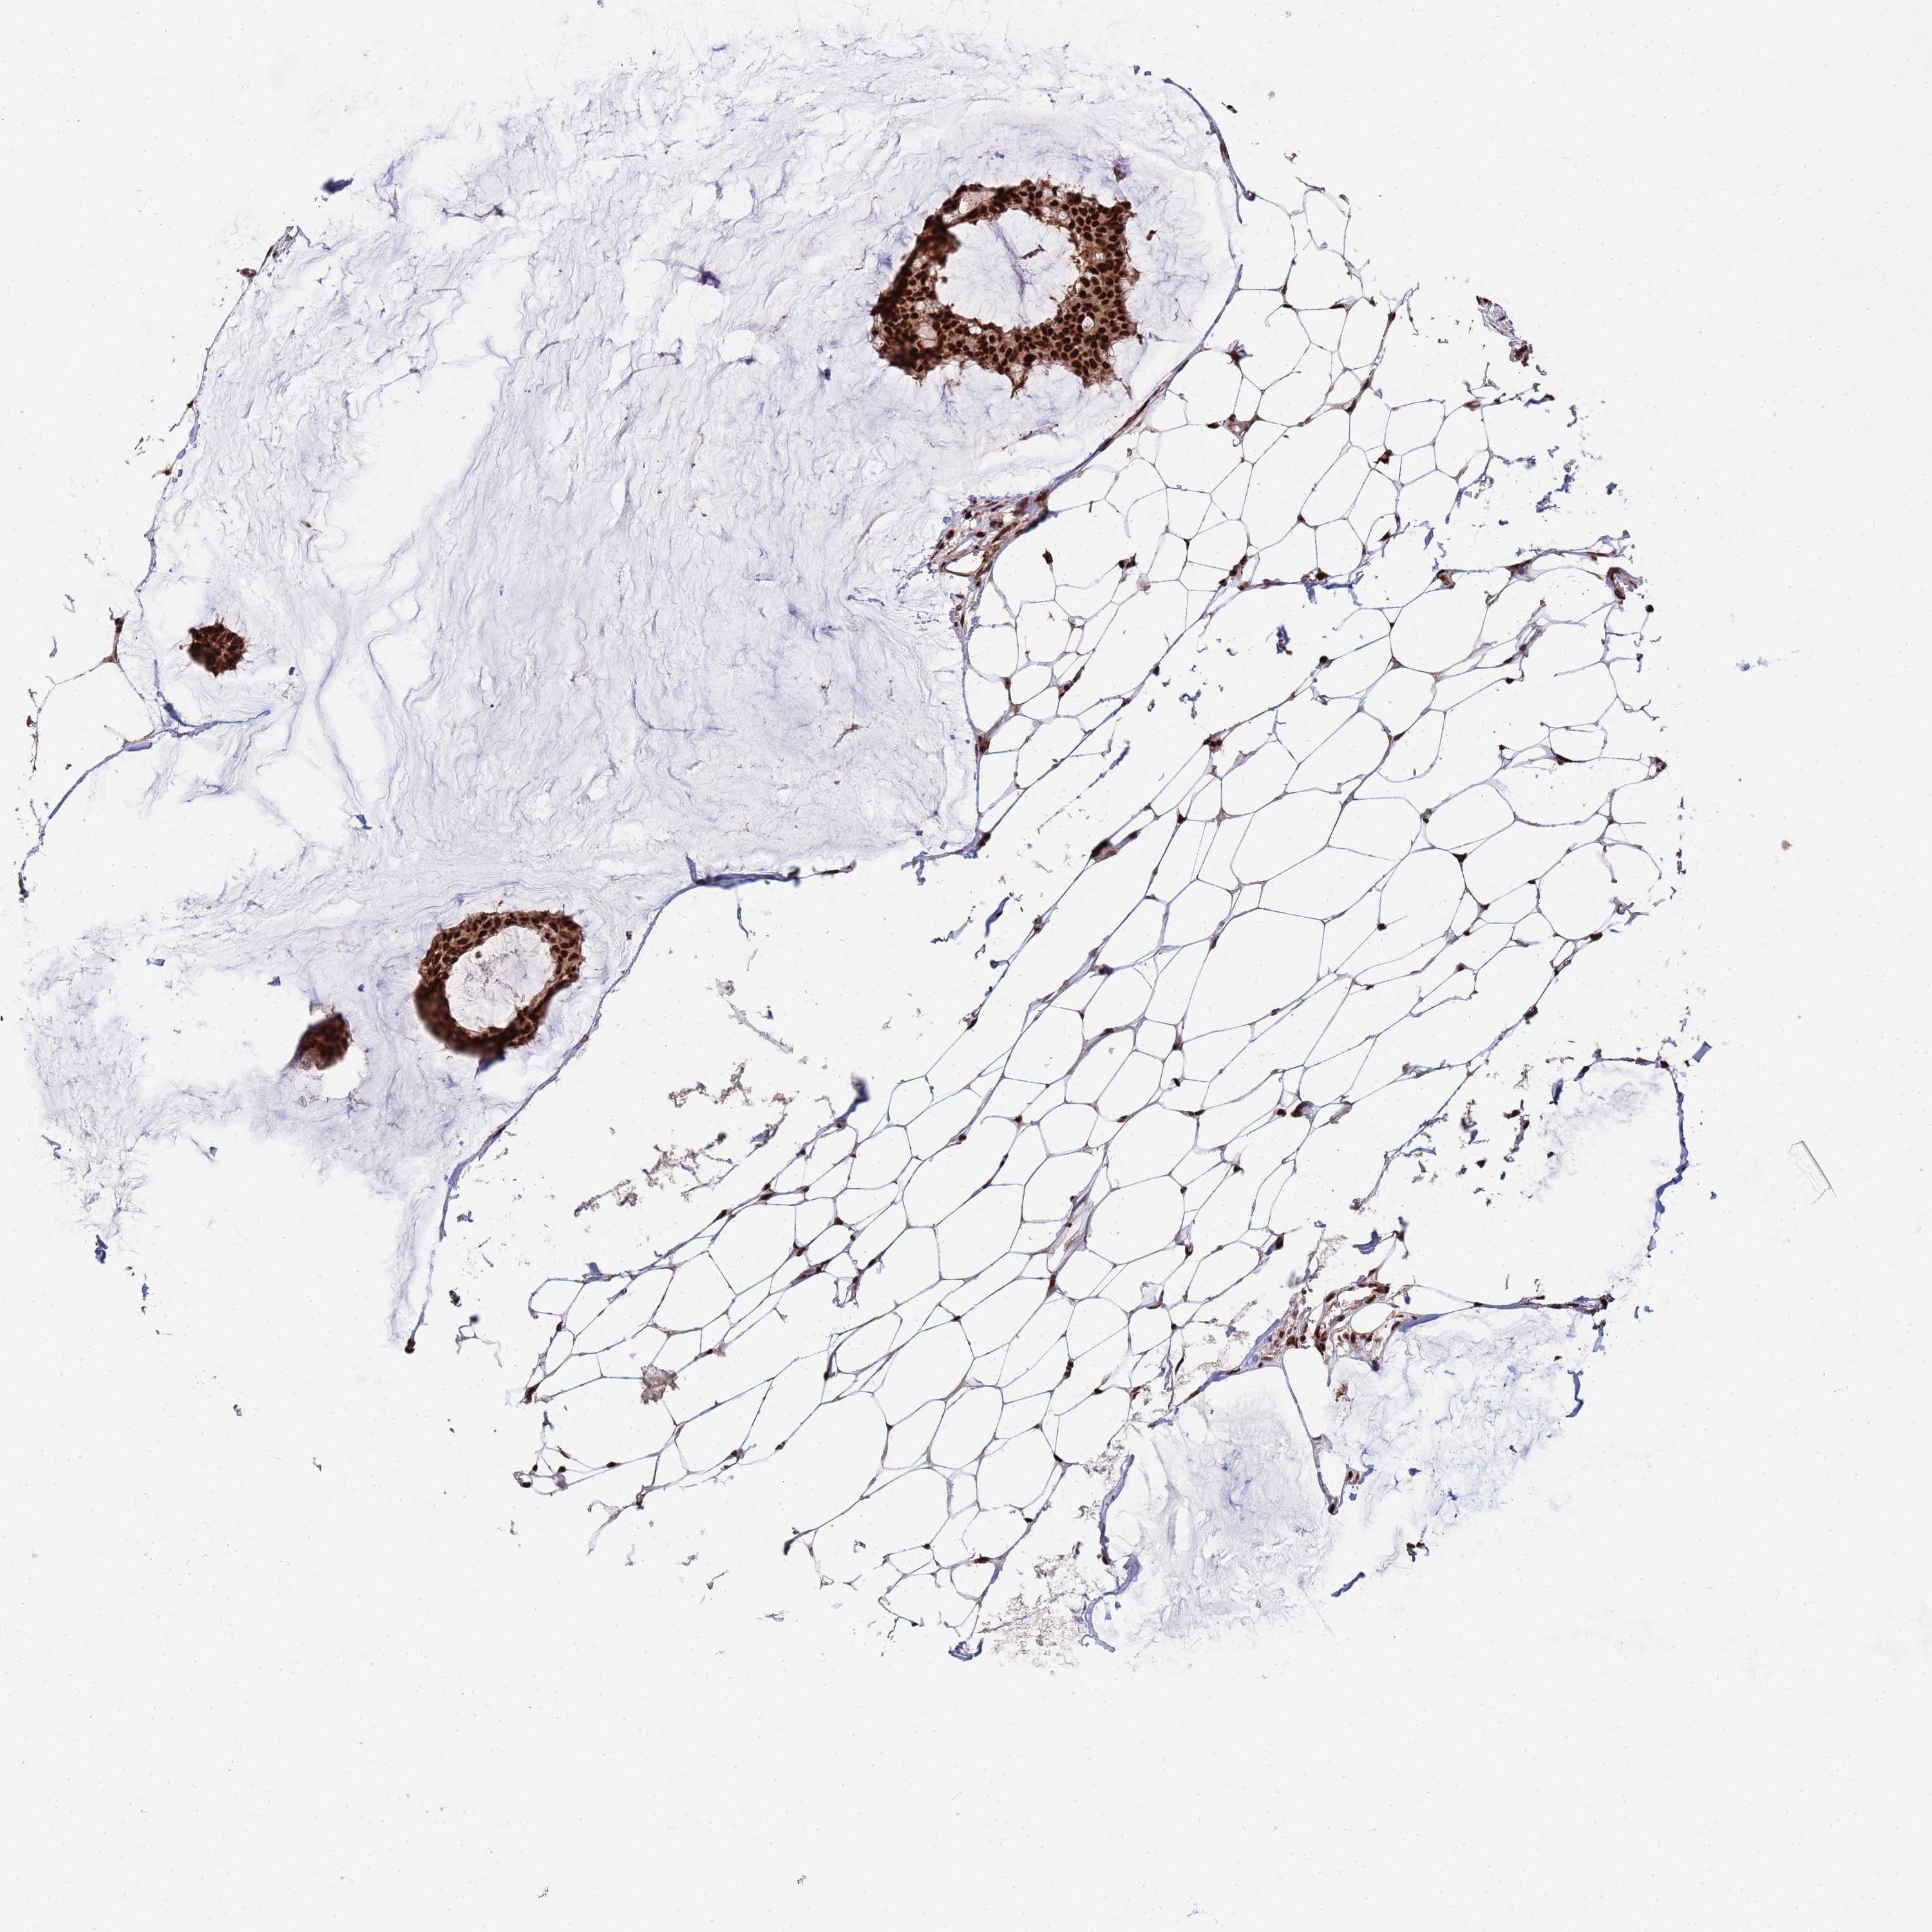

CANCER BREAST CANCER Show tissue menu

BRCA TCGA BRCA VALIDATION PROTEIN EXPRESSION